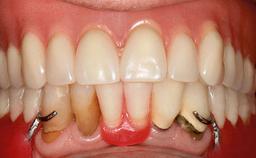

Improving an Existing Implant-supported Denture in an Alzheimer Patient with Bipolar Affective Disorder with Moderate Depression and Dementia

An 83-year-old man presented together with his caregiver at the dental department of the Medical University of Innsbruck, Austria with complaints of swelling in the right maxillary canine area and loss of retention of his 5-years-old mandibular denture. The patient had a significant medical history (20 years) of bipolar affective disorder with moderate depression (F 31.3) and dementia in Alzheimer’s disease (F 00.2). The patient had been in ambulant psychiatric therapy for his depressive illness for the past 20 years. He lived alone and had no children; his sister assisted with daily living. She reported that the patient exhibited compulsive hoarding behavior. In the previous two months, she had noted increasing disorientation and vertigo in the patient. She therefore accompanied him for a medical consultation at the Department of Psychiatry and Psychotherapy of the Medical University of Innsbruck. He was released home after a 6-week inpatient stay.

Infection at Implant Site None Chronic Acute

Periodontal Status History of periodontitis or genetic predisposition

Oral Hygiene and Compliance Insufficient